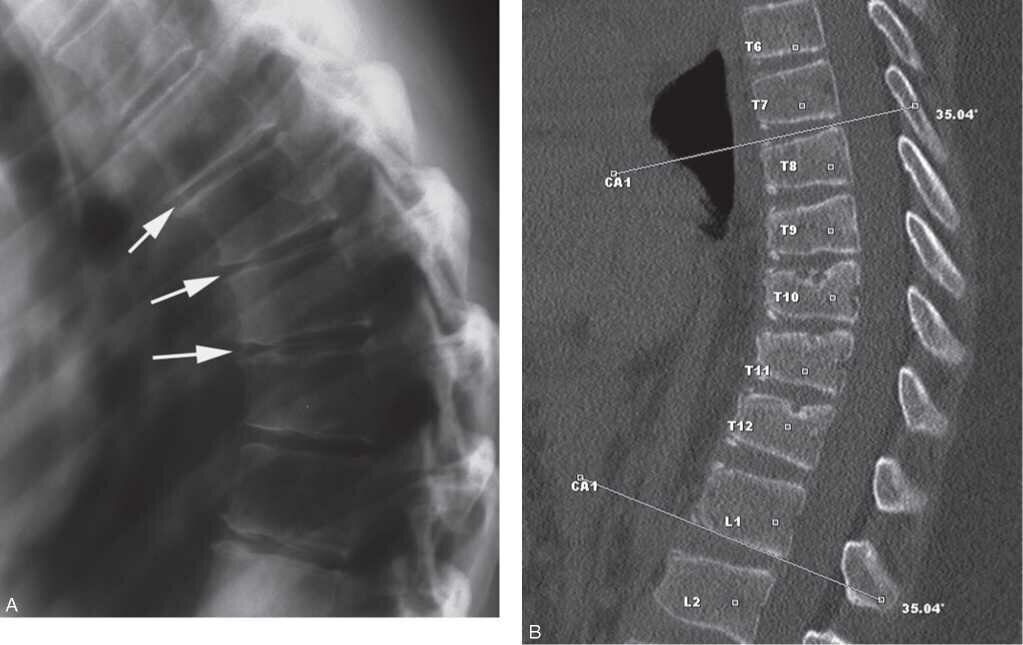

Нет ли деформации грудных позвонков (на рентгеновском снимке)

болезнь Шеермана-Мау

Если деформации позвонков нет, можно бороться за уменьшение выраженности кифоза. Если есть, бороться тоже нужно, но не за уменьшение кифоза, а за максимальную компенсацию (создание условий для сосудов, нервов, органов). Если такие выраженные изменения сохраняются длительное время, то уменьшение кифоза может дать новый пласт проблем. Если представить, что позвоночный столб - это стрелковый лук, а органы, сосуды и нервы - тетива этого лука, которая крепится к нему и создаёт такое напряжение, что лук изгибается. И вот мы решим, что нам не нравится такой гиперкифоз, сколиоз и начнём вытягивать позвоночник во что бы то ни стало. При насильном выпрямлении нашего лука тетива может не выдержать и начнёт повреждаться. Любое повреждение в организме вызывает неспецифическую защитную реакцию - воспаление! А признаки воспаления нам хорошо известны (покраснение, отёк, повышение температуры, боль, нарушение функции).